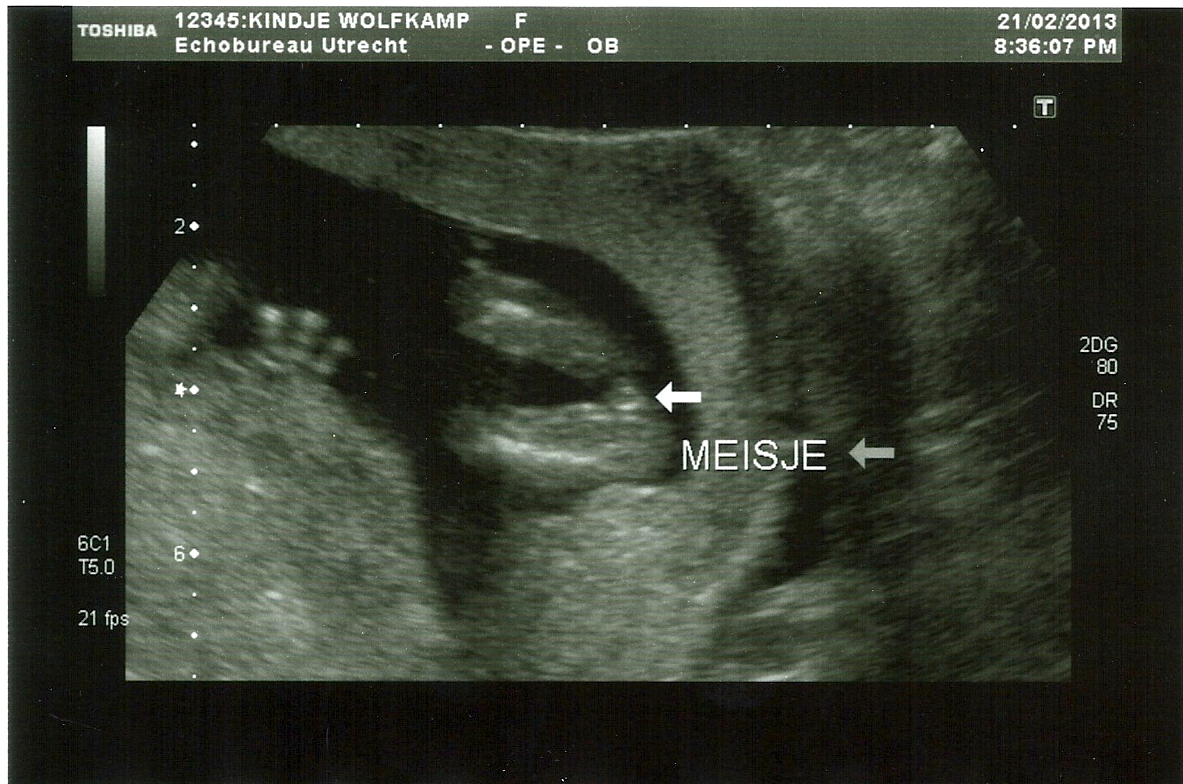

Thread updated with confirmed 15w u/s girl pictures :-)

Attachment 9167